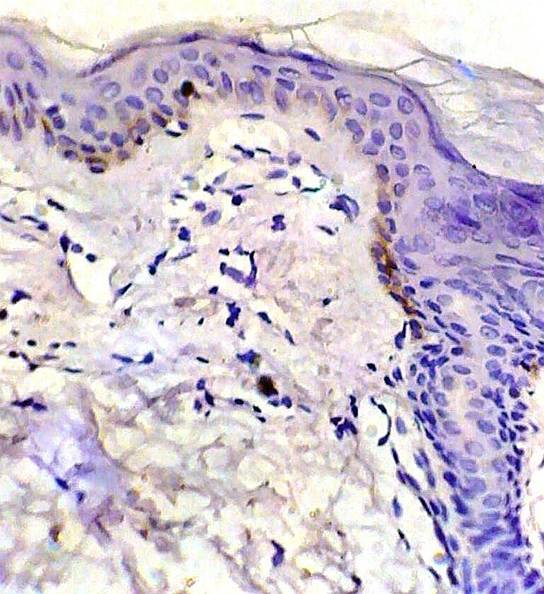

Fig 1: Control skin showing weak p53 expression. (ABC, Meyer s HX counter stain x 400)